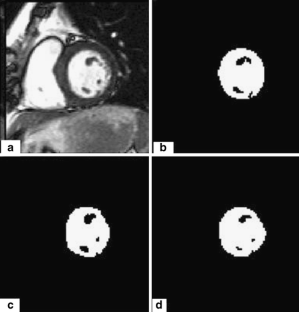

Segmentation of the left ventricle in MRI images is a task with important diagnostic power. Currently, the evaluation of cardiac function involves the global measurement of volumes and ejection fraction. This evaluation requires the segmentation of the left ventricle contour. In this paper, we propose a new method for automatic detection of the endocardial border in cardiac magnetic resonance images, by using a level set segmentation-based approach. To initialize this level set segmentation algorithm, we propose to threshold the original image and to use the binary image obtained as initial mask for the level set segmentation method. For the localization of the left ventricular cavity, used to pose the initial binary mask, we propose an automatic approach to detect this spatial position by the evaluation of a metric indicating object’s roundness. The segmentation process starts by the initialization of the level set algorithm and ended up through a level set segmentation. The validation process is achieved by comparing the segmentation results, obtained by the automated proposed segmentation process, to manual contours traced by tow experts. The database used was containing one automated and two manual segmentations for each sequence of images. This comparison showed good results with an overall average similarity area of 97.89%.

Fig. 2